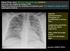

Opacités parenchymateuses hétrogènes non systématisées à contours flous; prédominance périhilaire et dans les régions supérieures

Femme 32 ans, obèse, détresse respiratoire aiguë subfébrile avec mise sous oxygène au masque à 50%. Apparition progressive des symptômes sur plusieurs jours. Test diagnostic grippe A positif. Lymphopénie